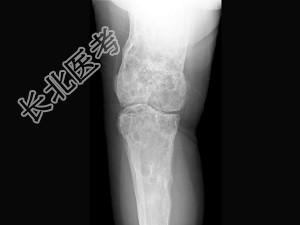

- 单项选择题女,42岁, 双下肢疼痛,结合图像, 最可能的诊断是 ( )

A、Paget病

B、内生软骨瘤

C、非骨化性纤维瘤

D、骨巨细胞瘤

E、骨纤维异常增殖症